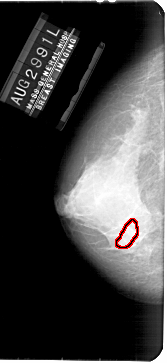

A_1927_1.LEFT_CC

LEFT_CC LINES 5431 PIXELS_PER_LINE 2491 BITS_PER_PIXEL 12 RESOLUTION 43.5 OVERLAY

FILE: A_1927_1.LEFT_CC.OVERLAY

TOTAL_ABNORMALITIES 1

ABNORMALITY 1

LESION_TYPE CALCIFICATION TYPE PLEOMORPHIC DISTRIBUTION CLUSTERED

ASSESSMENT 4

SUBTLETY 2

PATHOLOGY BENIGN

TOTAL_OUTLINES 1

BOUNDARY